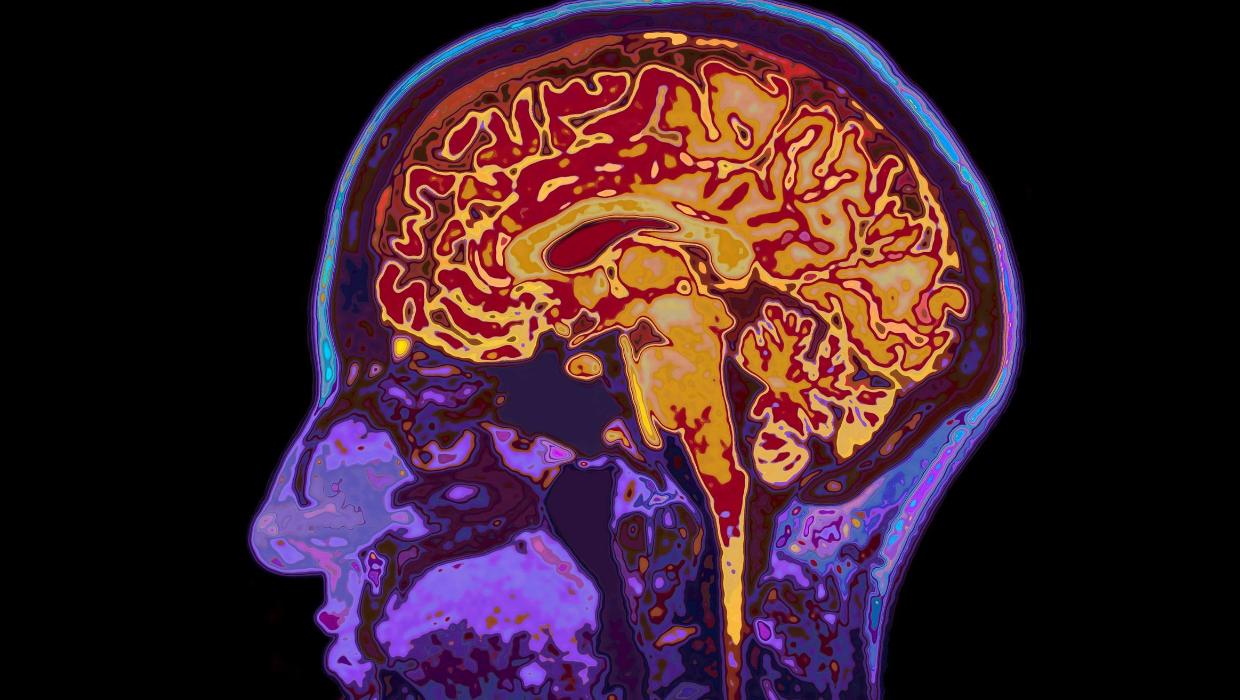

A new study conducted by the University of Cambridge has uncovered that the human brain continues to develop into early adulthood, with full maturation occurring around the age of 32. The research identifies five distinct epochs of brain development, highlighting four significant turning points throughout a person’s life.

The findings suggest that while many consider adolescence to conclude in the late teens, brain development continues to evolve well into the thirties. This challenges the traditional views on cognitive maturity and suggests a longer period of brain plasticity, which refers to the brain’s ability to adapt and change based on experiences and learning.

According to the study, the brain undergoes major transformations at specific ages. The first major shift occurs during early childhood, followed by significant changes in the teenage years. The next critical period is around the age of 26, when substantial reorganization takes place. Finally, the brain enters a decline phase starting at approximately age 66, indicating a marked change in cognitive functions.